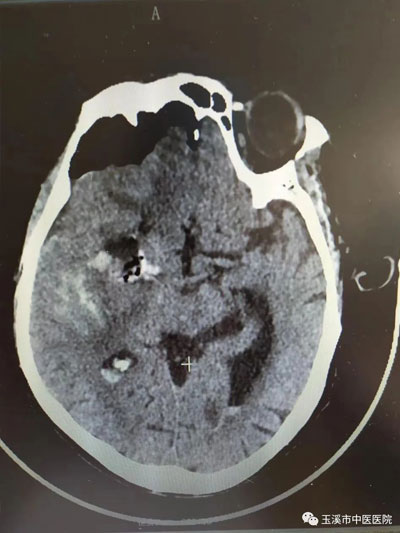

手術(shù)后顱內(nèi)血腫基本清除。